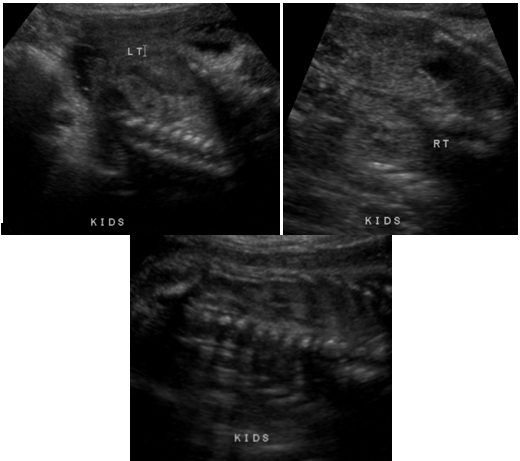

Multiple obstetric ultrasounds were performed throughout the pregnancy, which all focused on fetal abnormalities including: obstetric ultrasound at 27 weeks 6 days gestation, which showed micrognathia, echogenic kidneys and echogenic bowel Figure (1-3) as well as a three week discrepancy between the estimated ultrasound age and the gestational age by LMP, compatible with IUGR (Figure 4).

Figure 1 Ultrasound image from obstetric ultrasound at 27 weeks 6 days gestation showing: Echogenic kidneys bilaterally.

Figure 2 Ultrasound image from obstetric ultrasound at 27 weeks 6 days gestation showing: Echogenic bowel.

Figure 3 Ultrasound image from obstetric ultrasound at 27 weeks 6 days gestation showing: Suspected micrognathia.